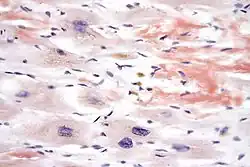

In histology and microscopy, Congo red is used for staining in amyloidosis, and for the cell walls of plants and fungi, and for the outer membrane of Gram-negative bacteria. Apple-green birefringence of Congo red stained preparations under polarized light is indicative of the presence of amyloid fibrils. Additionally, Congo red is used for the diagnostics of the Shigella flexneri serotype 2a, where the dye binds the bacterium's unique lipopolysaccharide structure. Furthermore, Congo red may also be used to induce expression of the type III secretion system of Shigella flexneri, bringing about the secretion of IpaB and IpaC, which form translocation pores within host cell membrane, allowing effector proteins to pass through and alter the host cell's biochemistry. The dye can also be used in flow cytometry experiments for the detection of Acanthamoeba, Naegleria and other amoebal cysts. In confocal microscopy, Congo red can be used as a stable fluorescent stain.[5]